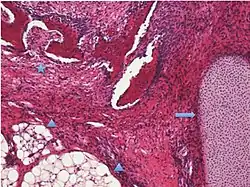

| Sex cord-stromal tumor | Ovarian fibroma | 1.5% | 0% | Spindle-shaped fibroblastic cells and abundant collagen.[11] |